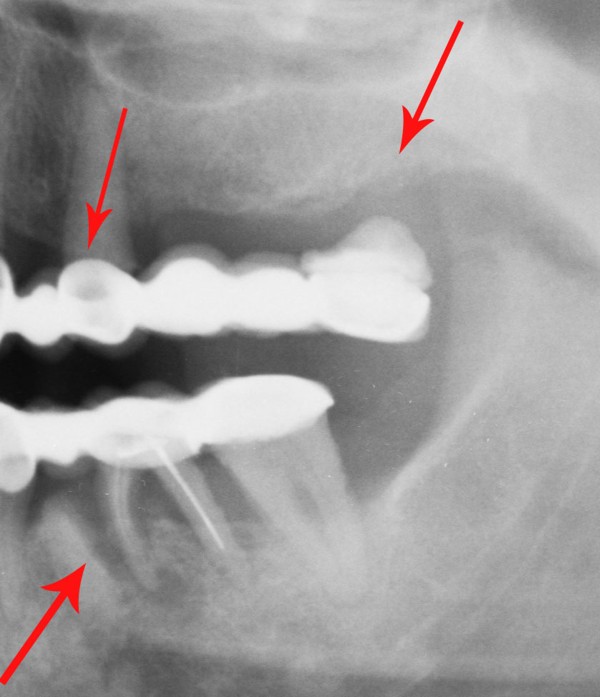

MUCHO SE HA HABLADO HASTA HOY DE LOS DISTINTOS ESQUEMAS OCLUSALES A USAR. SIN EMBARGO , HAY ALGO DE QUE ADOLECEN LAS LOS TRABAJOS PROTÉTICOS OBSERVADOS EN MÚLTIPLES LABORATORIOS DE NUESTRO MEDIO , COMO ASI DE MUCHAS PUBLICACIONES DE LOS ÚLTIMOS TIEMPOS , OLVIDANDO UN CONCEPTO TAN BÁSICO COMO EVIDENTE: PARA QUE SIRVEN LOS DIENTES. OBSERVAMOS A MENUDO GRANDES ELEVACIONES DE SENO A FIN DE LOGRAR IMPLANTAR LO IMPOSIBLE….LATERALIZACIONES DE NERVIO DENTARIO INFERIOR CON FINES SIMILARES…EXTENSAS PRÓTESIS CANTILEVER PARA REPONER LA CASI TOTALIDAD DE UNA ARCADA…Y UN SINFÍN DE RECURSOS QUE SE ACERCAN AL CRITERIO DE «ALGO HAY QUE PONER…» Y SE ALEJAN DEL SERIO SENTIDO DE «REHABILITAR». SABEMOS QUE SON MÚLTIPLES LAS FUNCIONES QUE EL SISTEMA DENTARIO CUMPLE, PERO LA FUNDAMENTAL ES MASTICAR. EN ESE SENTIDO DESDE LOS RUMIANTES, HASTA LOS CARNÍVOROS TIENEN SUS PROPIOS PATRONES A SEGUIR. EN EL CASO DEL HOMBRE, CON UNA ARTICULACIÓN TEMPOROMANDIBULAR TAN COMPLEJA Y PAUSIBLE DE DISFUNCIONES, COMO DE UN COMPLEJO MUSCULAR NECESITADO DE UNA LONGITUD ADECUADA PARA SU ORTOFUNCIÓN, LA CAPACIDAD DE MASTICAR SE VE A MENUDO ALTERADA POR LOS INNUMERABLES TRABAJOS PROTÉTICOS QUE A DIARIO SE REALIZAN EN EL MUNDO, QUE CARECEN DE LOS PATRONES NECESARIOS PARA QUE ESA FUNCIÓN SE DESARROLLE CORRECTAMENTE. LAS SUBFUNCIONES DE : INCIDIR-DESGARRAR-DISCERNIR EL ALIMENTO Y MOLER, ,PARA FINALMENTE DEGLUTIR, QUE CUMPLEN LAS DISTINTAS PIEZAS DENTARIAS , CONSTITUYEN UN CAPÍTULO DE LA ODONTOLOGÍA TAN BÁSICO Y EVIDENTE, COMO OLVIDADO . ES A MI CRITERIO FUNDAMENTAL ; PENSAR LAS DISTINTAS REHABILITACIONES ORALES POSIBLES, EN TÉRMINOS DE : EFICACIA MASTICATORIA CUANDO A MENUDO OBSERVAMOS CARAS PALATINAS DE LOS ANTERIORES CLARAMENTE CONVEXAS, O CUANDO LAS SUPERFICIES OCLUSALES DE LOS POSTERIORES SE CONSTRUYEN CON CÚSPIDES GRADO CERO, CON FINES DE MINIMIZAR LAS FUERZAS EXPULSIVAS DE UNA PRÓTESIS O LAS FUERZAS TANGENCIALES A LOS IMPLANTES, …LA EFICACIA MASTICATORIA, DISMINUYE SENSIBLEMENTE , CUANDO NO SE PROVOCAN DISFUNCIONES IATROGÉNICAS A VECES MAS DIFÍCILES DE RESOLVER QUE EL ESTADO INICIAL DE LA BOCA. DE LA MISMA MANERA, LA CONSERVACIÓN PROLONGADA DE PIEZAS EN ESTADO TERMINAL, MUCHAS VECES PROVOCA LA PÉRDIDA EXAGERADA DE HUESO ALVEOLAR, MANTENIENDO LOS MISMOS CON SUPRAESTRUCTURAS QUE AGRAVAN LA SITUACIÓN. SI BIEN ES CIERTO, QUE LA CONSERVACIÓN DE PIEZAS DENTARIAS , MUCHAS VECES EN «ESTADO CAÓTICO», NOS SIRVEN PARA SOPORTAR ELEMENTOS PROVISIONALES DE ALTA EFICACIA DURANTE EL TRATAMIENTO REHABILITADOR….Y QUE LAS MISMAS ADQUIEREN ESTADOS MUCHO MAS BENÉFICOS DURANTE SU PROVISORIA FUNCIÓN, TAMBIÉN ES CIERTO, QUE CON VISTAS A UNA MAYOR «EFICACIA MASTICATORIA», LA CONSERVACIÓN DEL HUESO RESIDUAL POST EXTRACCIÓN, ADECUADAMENTE TRATADO , SUELE SER DE MAS UTILIDAD , QUE LA CONSERVACIÓN PROLONGADA DE ELEMENTOS DENTARIOS ALTAMENTE DESTRUIDOS. SALZMAN, EN 1.947 COMPROBÓ QUE PUEDE NO EXISTIR EL MOVIMIENTO HORIZONTAL MANDIBULAR DURANTE LA MASTICACIÓN DE ALIMENTOS BLANDOS, MIENTRAS QUE LOS ALIMENTOS DUROS QUE NECESITAN MAS PRESIÓN, DAN FORZOZAMENTE LUGAR A LA TRANSTRUSIÓN. JANKELSON, HOFFMAN Y HENDRON, EN 1.953, ESTABLECIERON QUE LA MASTICACIÓN, BILATERAL ALTERNADA, ERA NECESARIA PARA LA MANUTENCIÓN DE LAS ESTRUCTURAS DE SOPORTE, Y QUE LAS MASTICACIONES UNILATERALES O PROTRUSIVAS ERAN PRODUCTO DE INTERFERENCIAS OCLUSALES. CIERTOS ESTUDIOS REALIZADOS CON CINEFLUOROSCOPÍA HAN DEMOSTRADO QUE NO EXISTE NINGÚN CONTACTO DENTARIO DURANTE LA MASTICACIÓN . NO OBSTANTE ADAMS Y ZANDER EN 1.964, CON MÉTODOS DE BASADOS EN LA MULTIPLICIDAD DE ESTUDIOS PRODUCIDOS ACERCA DE LA FISIOLOGÍA DE LA MASTICACIÓN , ES IMPENSABLE HOY, A LA ALTURA DE LOS CONOCIMIENTOS ACTUALES , ESCAPAR A LA NORMA INELUDIBLE DE FORMA = FUNCIÓN POR ELLO ES NECESARIO , ANALIZAR LAS REHABILITACIONES EN FORMA GLOBAL E INTESIVAMENTE , YA QUE , POR EJEMPLO , LA SIMPLE INSTALACIÓN DE IMPLANTES DENTALES , POR MUY INTEGRADOS QUE ESTEN , DE NADA SIRVEN SI NO EXISTE UNA CONGRUENCIA ENTRE LAS FORMAS QUE CUMPLAN LAS FUNCIONES ESPECÍFICAS PARA LAS CUALES HA SIDO CREADO EL SISTEMA. EN LAS SIGUIENTES FOTOGRAFÍAS PERTENECIENTES A UN MISMO CASO , SE OBSERVA CLARAMENTE QUE SI BIEN SE HAN COLOCADO LAS PIEZAS FALTANTES EN UN ÁREA EDÉNTULA , DE POCO SERVIRÁN YA QUE LA GUIA CANINA DEL LADO OPUESTO ES INEXISTENTE, ADEMÁS DE QUE LAS SUPERFICIES OCLUSALES DIFÍCILMENTE CUMPLAN CON LA EFICACIA MASTICATORIA. EN LA MASTICACIÓN OMNÍVORA LOS CONTACTOS OCLUSALES SON INEXISTENTES SALVO EN LA ÚLTIMA FASE DEL CICLO MASTICATORIO. EL CICLO MASTICATORIO CONSTA DE DISTINTAS FASES DE LAS CUALES LA INICIAL , CONSISTE EN LA: POSTERIORMENTE , LA MANDIBULA EJERCE UN MOVIMIENTO LATERAL HACIA EL LADO (LADO DE TRABAJO) DONDE SE HA UBICADO EL ALIMENTO : A CONTINUACIÓN LA MANDIBULA LATERALIZADA COMIENZA EL CIERRE , HASTA CONTACTAR LOS CANINOS ENTRE SI : DONDE EL SUPERIOR SEÑALA EL CAMINO A SEGUIR DEL CANINO INFERIOR (QUE ES SOLIDARIO A LA MANDIBULA TODA), DESDE EL PUNTO DEL PRIMER CONTACTO (BORDE A BORDE CANINO , O SUS CERCANÍAS ), HASTA AQUEL PUNTO TERMINAL ,DEL RECORRIDO CANINO QUE SEÑALA LA: …….. DEL RESTO DE LAS PIEZAS. DURANTE ESA APROXIMACIÓN HACIA LA MÁXIMA INTERCUSPIDACIÓN ( LO QUE ES LO MISMO QUE HACIA LA RELACIÓN CÉNTRICA EN UNA OCLUSIÓN ORGÁNICA..) , LOS REBORDES MARGINALES MESIALES Y DISTALES , JUNTO A LAS TRIANGULARES INTERNAS DE LAS PIEZAS POSTERIORES DESBRIDAN EL ALIMENTO EN CICLOS CADA VEZ MAS PEQUEÑOS, A MEDIDA QUE EL ALIMENTO SE DESTRUYE. LAS PIEZAS DENTARIAS SE VAN APROXIMANDO ENTRE SI CADA VEZ MAS , INTERDIGITANDO SUS CÚSPIDES , SEGÚN EL MECANISMO ANTERIOR , HASTA ALCANZAR UN BOLO ADECUADO PARA DEGLUTIR. DE LA MISMA MANERA QUE LO HACE UNA TIJERA. ASI, ES COMO ACTUAN LAS CÚSPIDES DENTARIAS ¿CUAL SERÁ ENTONCES EL EFECTO DE UNA MASTICACIÓN CARENTE ABSOLUTAMENTE DE ANATOMÍA? FRENTE A UNA MASTICACIÓN QUE OPERE SEGÚN: FORMA = FUNCIÓN ¿? ES EVIDENTE QUE LA INEFICACIA PRODUCTO DE LA FALTA DE ANATOMÍA ADECUADA REDUNDARÁ EN UN MAYOR ESFUERZO MASTICATORIO , Y SERÁ EL RESTO DEL APARATO DIGESTIVO QUIEN SE ENCARGUE DE LAS DESTRUCCIÓN DE LOS ALIMENTOS PARA QUE ESTOS SEAN DIGERIDOS. REHABILITAR LAS SUPERFICIES OCLUSALES , COMO ASI REPONERLAS CON UN CRITERIO ANATÓMICO FUNCIONAL , DONDE LA ALTURA CUSPÍDEA , LA GUÍA CANINA, LA CREACIÓN DE ESPACIOS UNIFORMES DURANTE EL FENÓMENO DE LUCE , LA DISCLUSIÓN ABSOLUTA DE TODAS LAS UNIDADES DE OCLUSIÓN DURANTE UNA TRANSTRUSIÓN , TANTO DEL LADO ACTIVO COMO DEL NO ACTIVO, EN ARMÓNICA CONGRUENCIA CON LA LONGITUD MUSCULAR Y EL FISIOLOGISMO ARTICULAR , CONSTITUYEN LAS BASES PARA CONSTRUIR REHABILITACIONES QUE REPONGAN Y MANTENGAN LA EFICACIA MASTICATORIA.

FIG 12